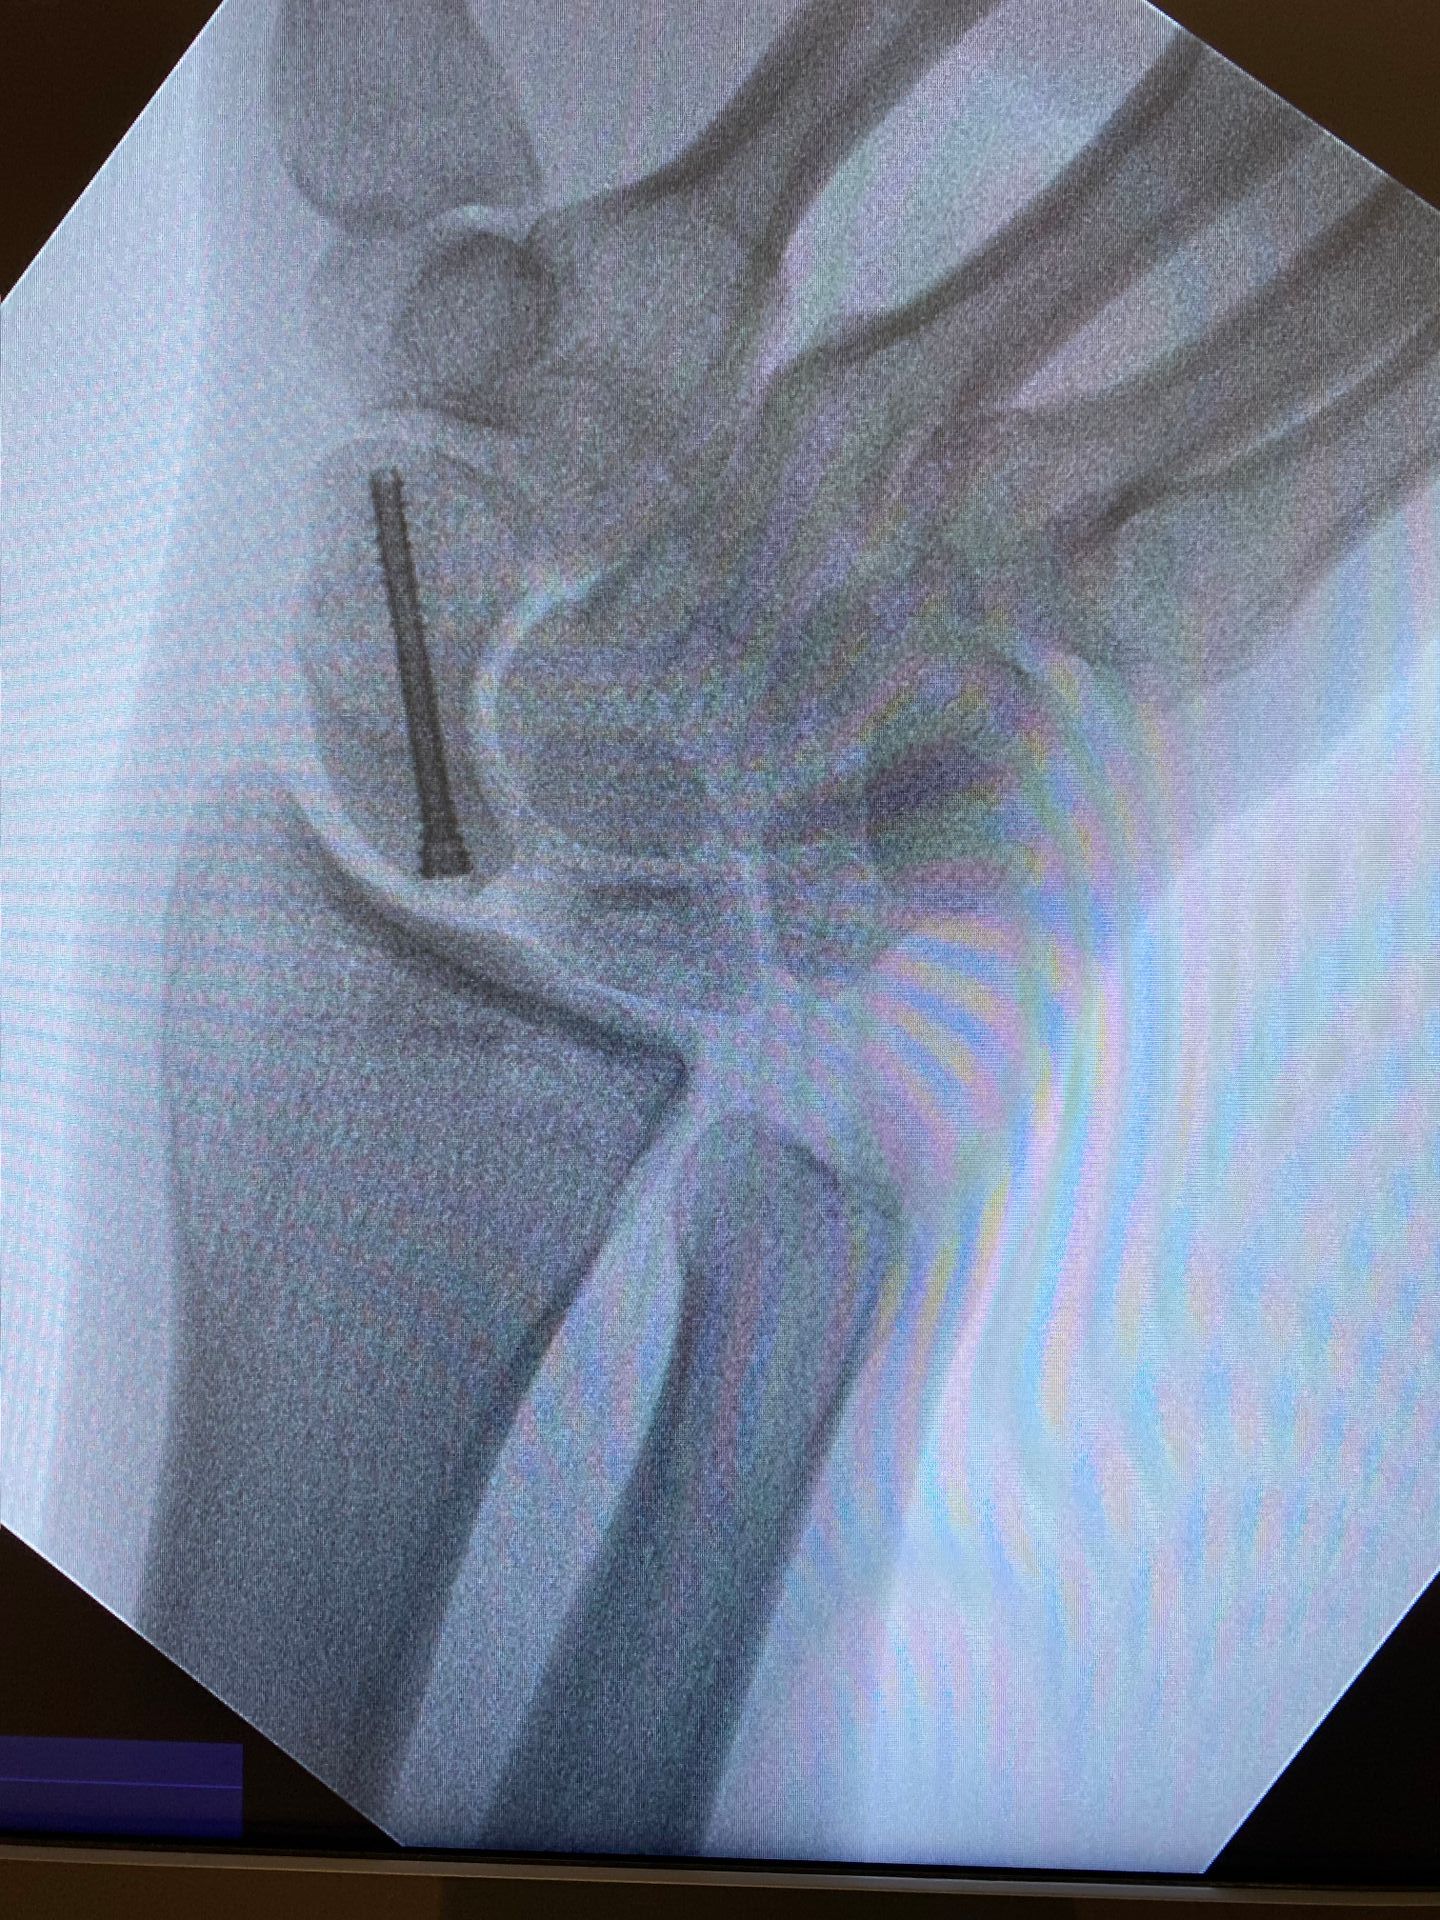

- De modo geral, o tratamento da fratura de escafóide será feito através do uso de um parafuso canulado inserido através de uma pequena incisão. Esse acesso pode ser na palma da mão ou no dorso do punho.

- Durante o ato cirúrgico, o cirurgião de mão utilizará um equipamento chamado radioscopia para guiar a introdução do fio guia e do parafuso. Através desse equipamento e de referências anatômicas, será definida a posição ideal do parafuso. Por exemplo, no plano coronal, um bom parâmetro radiográfico da posição distal do parafuso é o ⅓ da distância do lado radial do pólo distal do escafóide